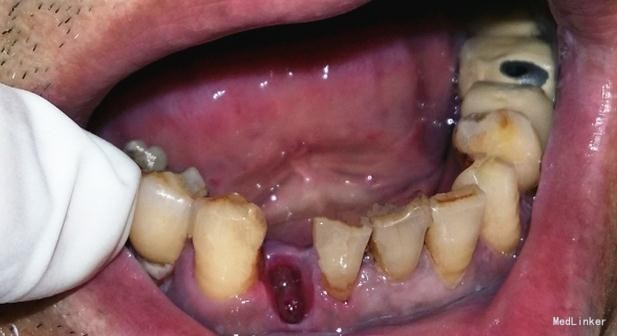

患者,男,45岁,右侧下颌侧切牙严重龋坏,拔除后要求种植修复,平素体质一般,无药物、食物过敏史,无高血压、心脏病等系统病史

牙科CT检查骨量适中,适合种植

种植修复

效果很好,患者满意